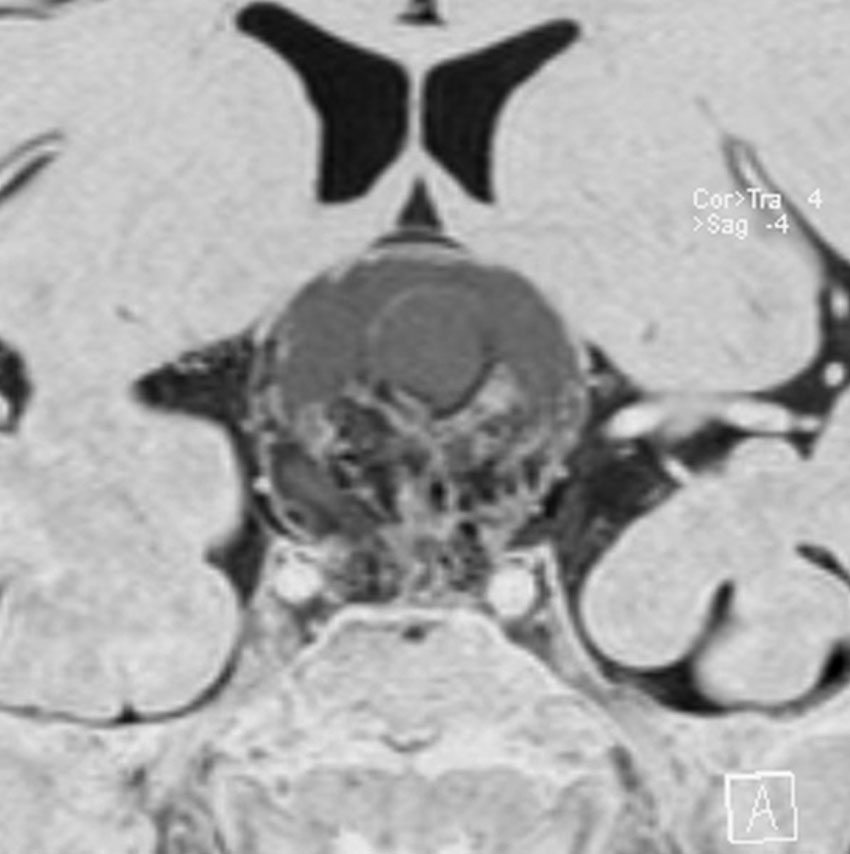

ちょっと大きな頭蓋咽頭腫です

嚢胞(液体が入っている袋)の部分と,腫瘍細胞が固まっている実質部分が入り交じっています。このくらいの大きさになってしまうと,下垂体機能を残すことはとても難しくなります。視神経が圧迫されて視力低下と視野障害を生じます。第3脳室が腫瘍で閉塞していて水頭症になっていますから知能の活動が低下します。

腫瘍を摘出するのに危ないのは,脳の血管の損傷です。左では白く,右では黒く線状に移っているのが太い脳動脈です。これら以外にもたくさんの細い重要な動脈が絡んでいます。

幸いこの患者さんの腫瘍は摘出できて患者さんは元気になりました。でもこのくらいのサイズになると手術がいつもうまくいくとは限りませんし重大な障害が残ることもあります。